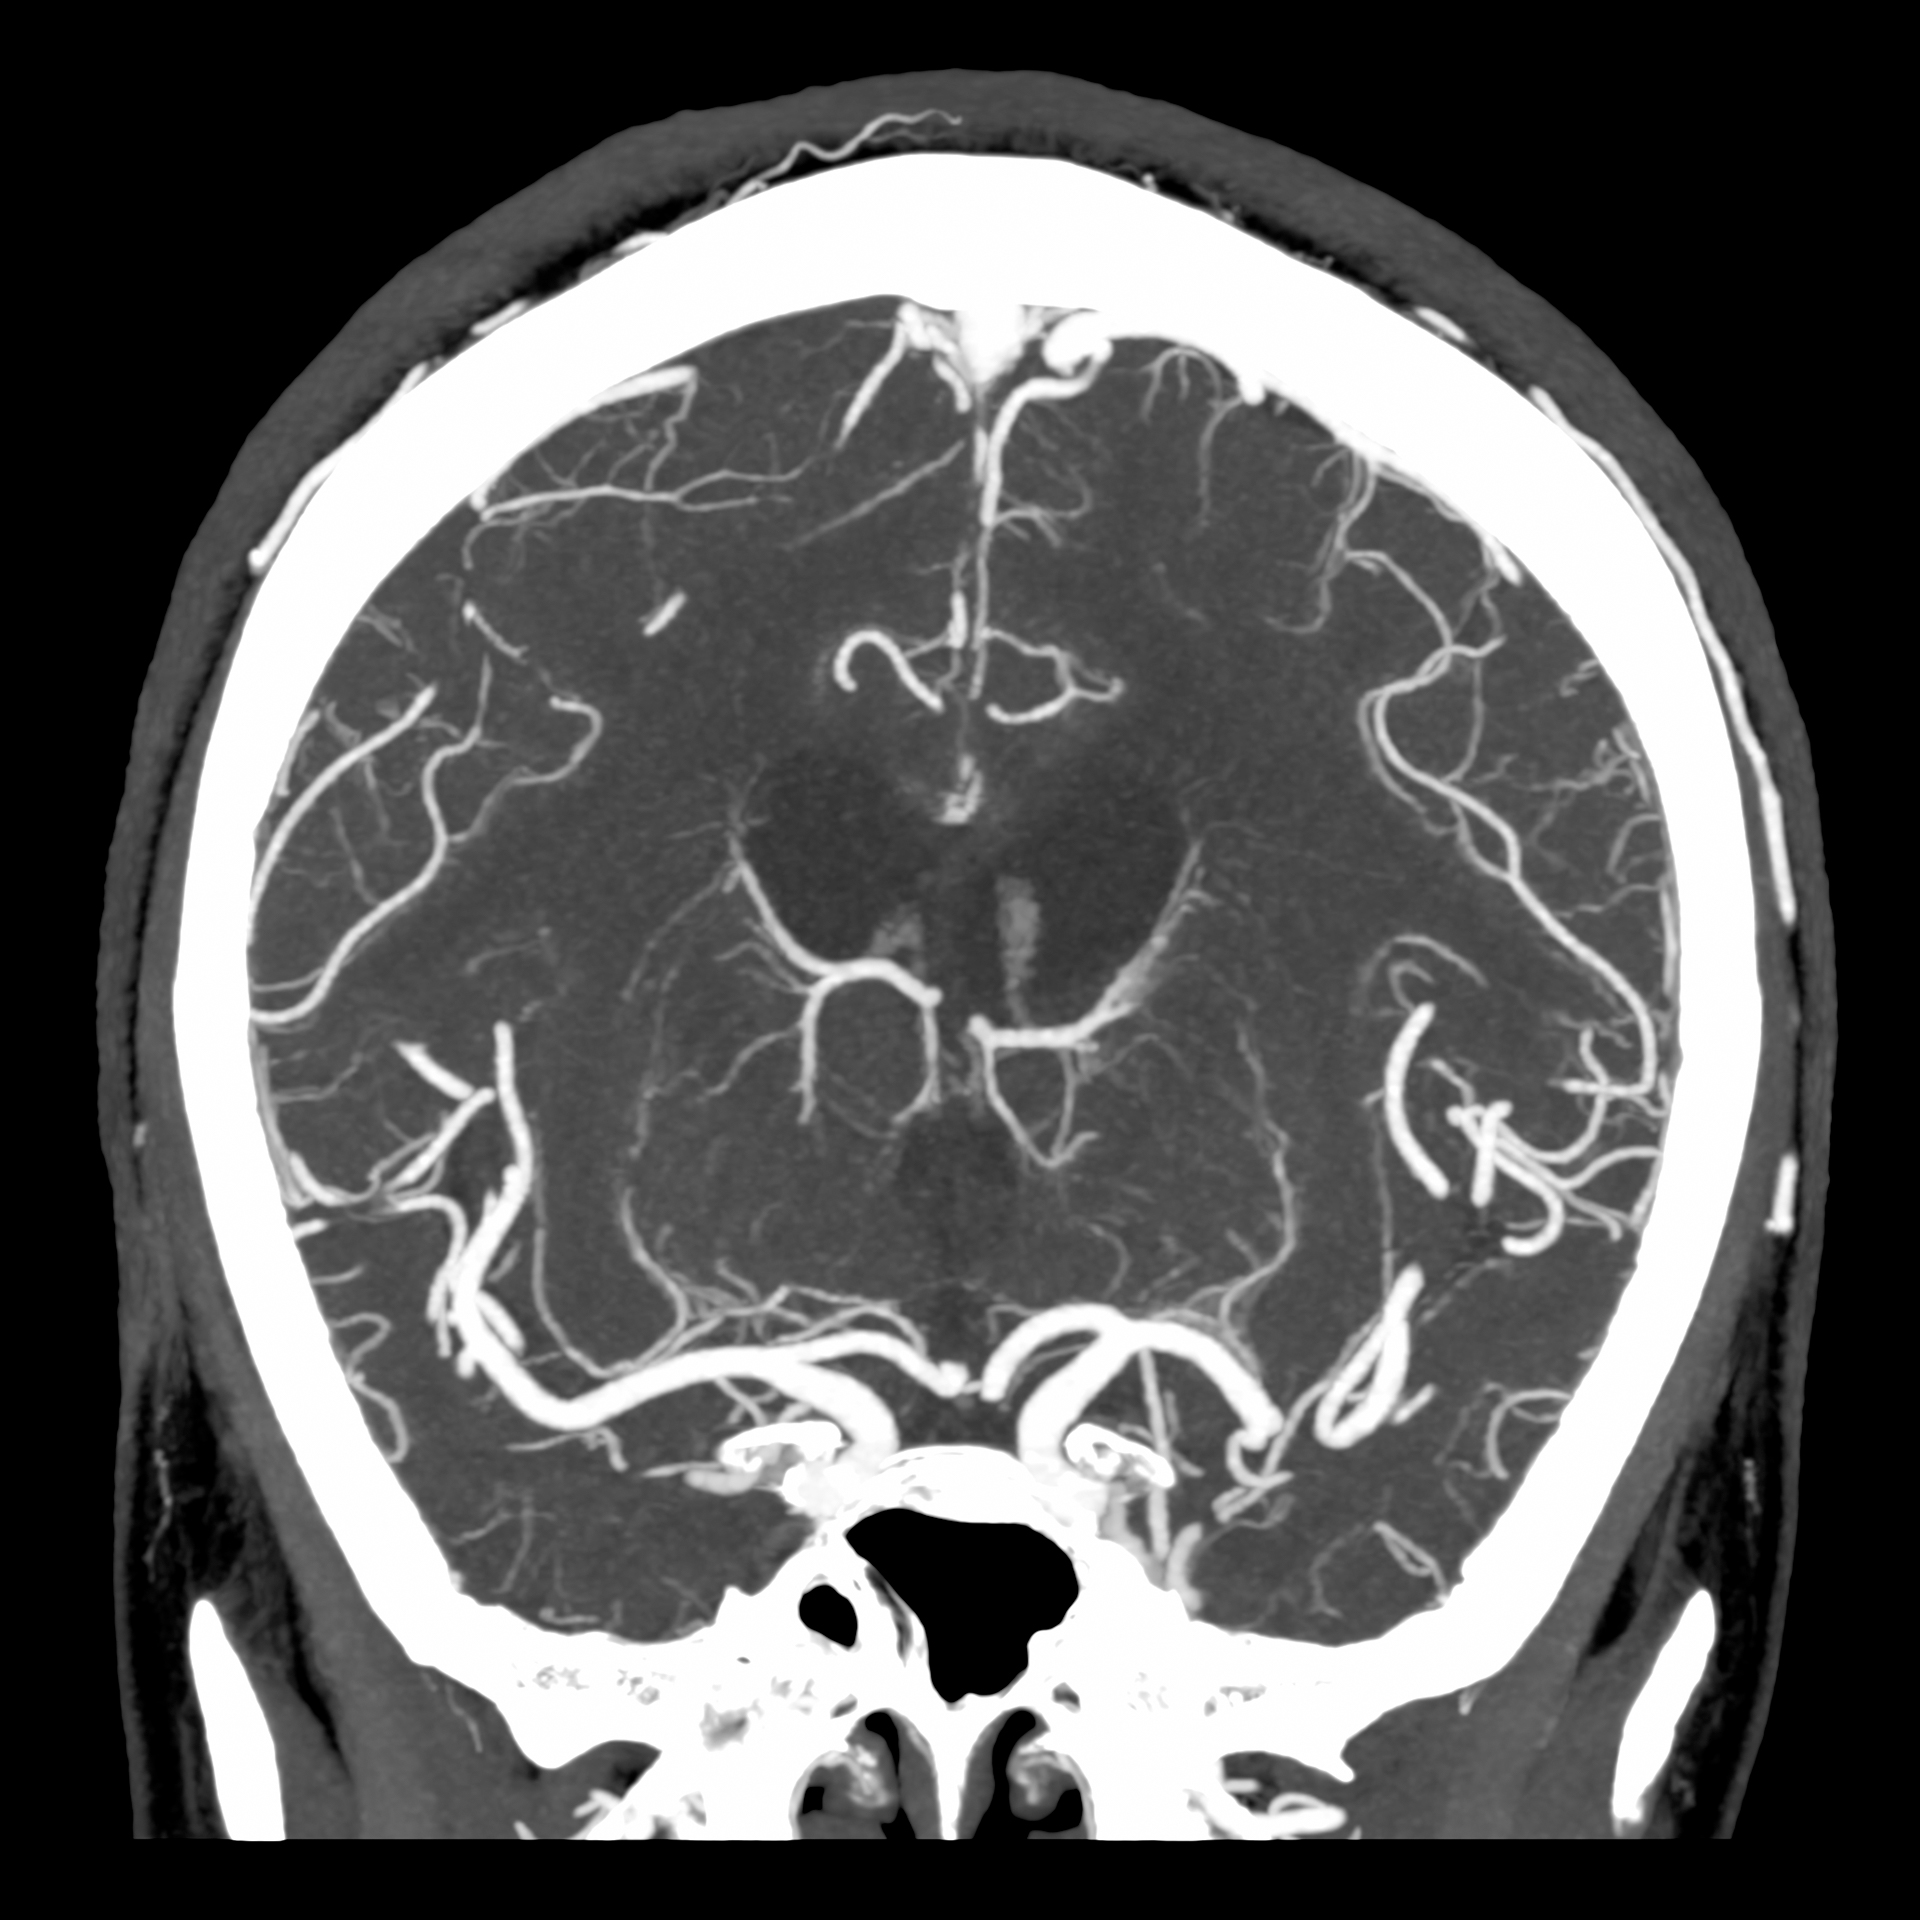

КТ ангіографія голови, 0,25 мм, 1024 матриця¹

Порівняння звичайної роздільної здатності з ультрависокою роздільною здатністю (УРЗ)²

Звичайна КТ 0,5 мм

КТ з ультрависокою роздільною здатністю 0,25 мм ³